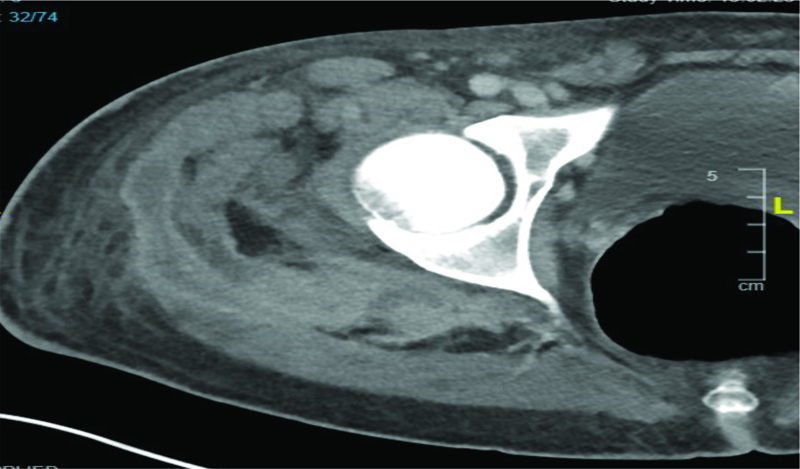

The patient returned to the emergency department about 4 weeks after completion of antibiotics with the same complaint of right hip pain and limited motion. Upon initial evaluation, he was hemodynamically stable but had features of sepsis. He was adequately resuscitated with fluid and started on broad spectrum antibiotics. A computed tomography (CT) scan of the hip on this admission showed an extensive osseous erosive lesion involving the right proximal femoral metaphysis. In addition, an extensive intramuscular organized enhancing fluid collection was present tracking along the fascial plane between the gluteus medius and gluteus maximus inferiorly into the lateral and posterior and medial deep compartments of the thigh. These results suggested osteomyelitis and abscess of the right hip.

Figure 1

Figure 1. Computed tomography scan of the hip of the patient showing features of osteomyelitis and abscess.